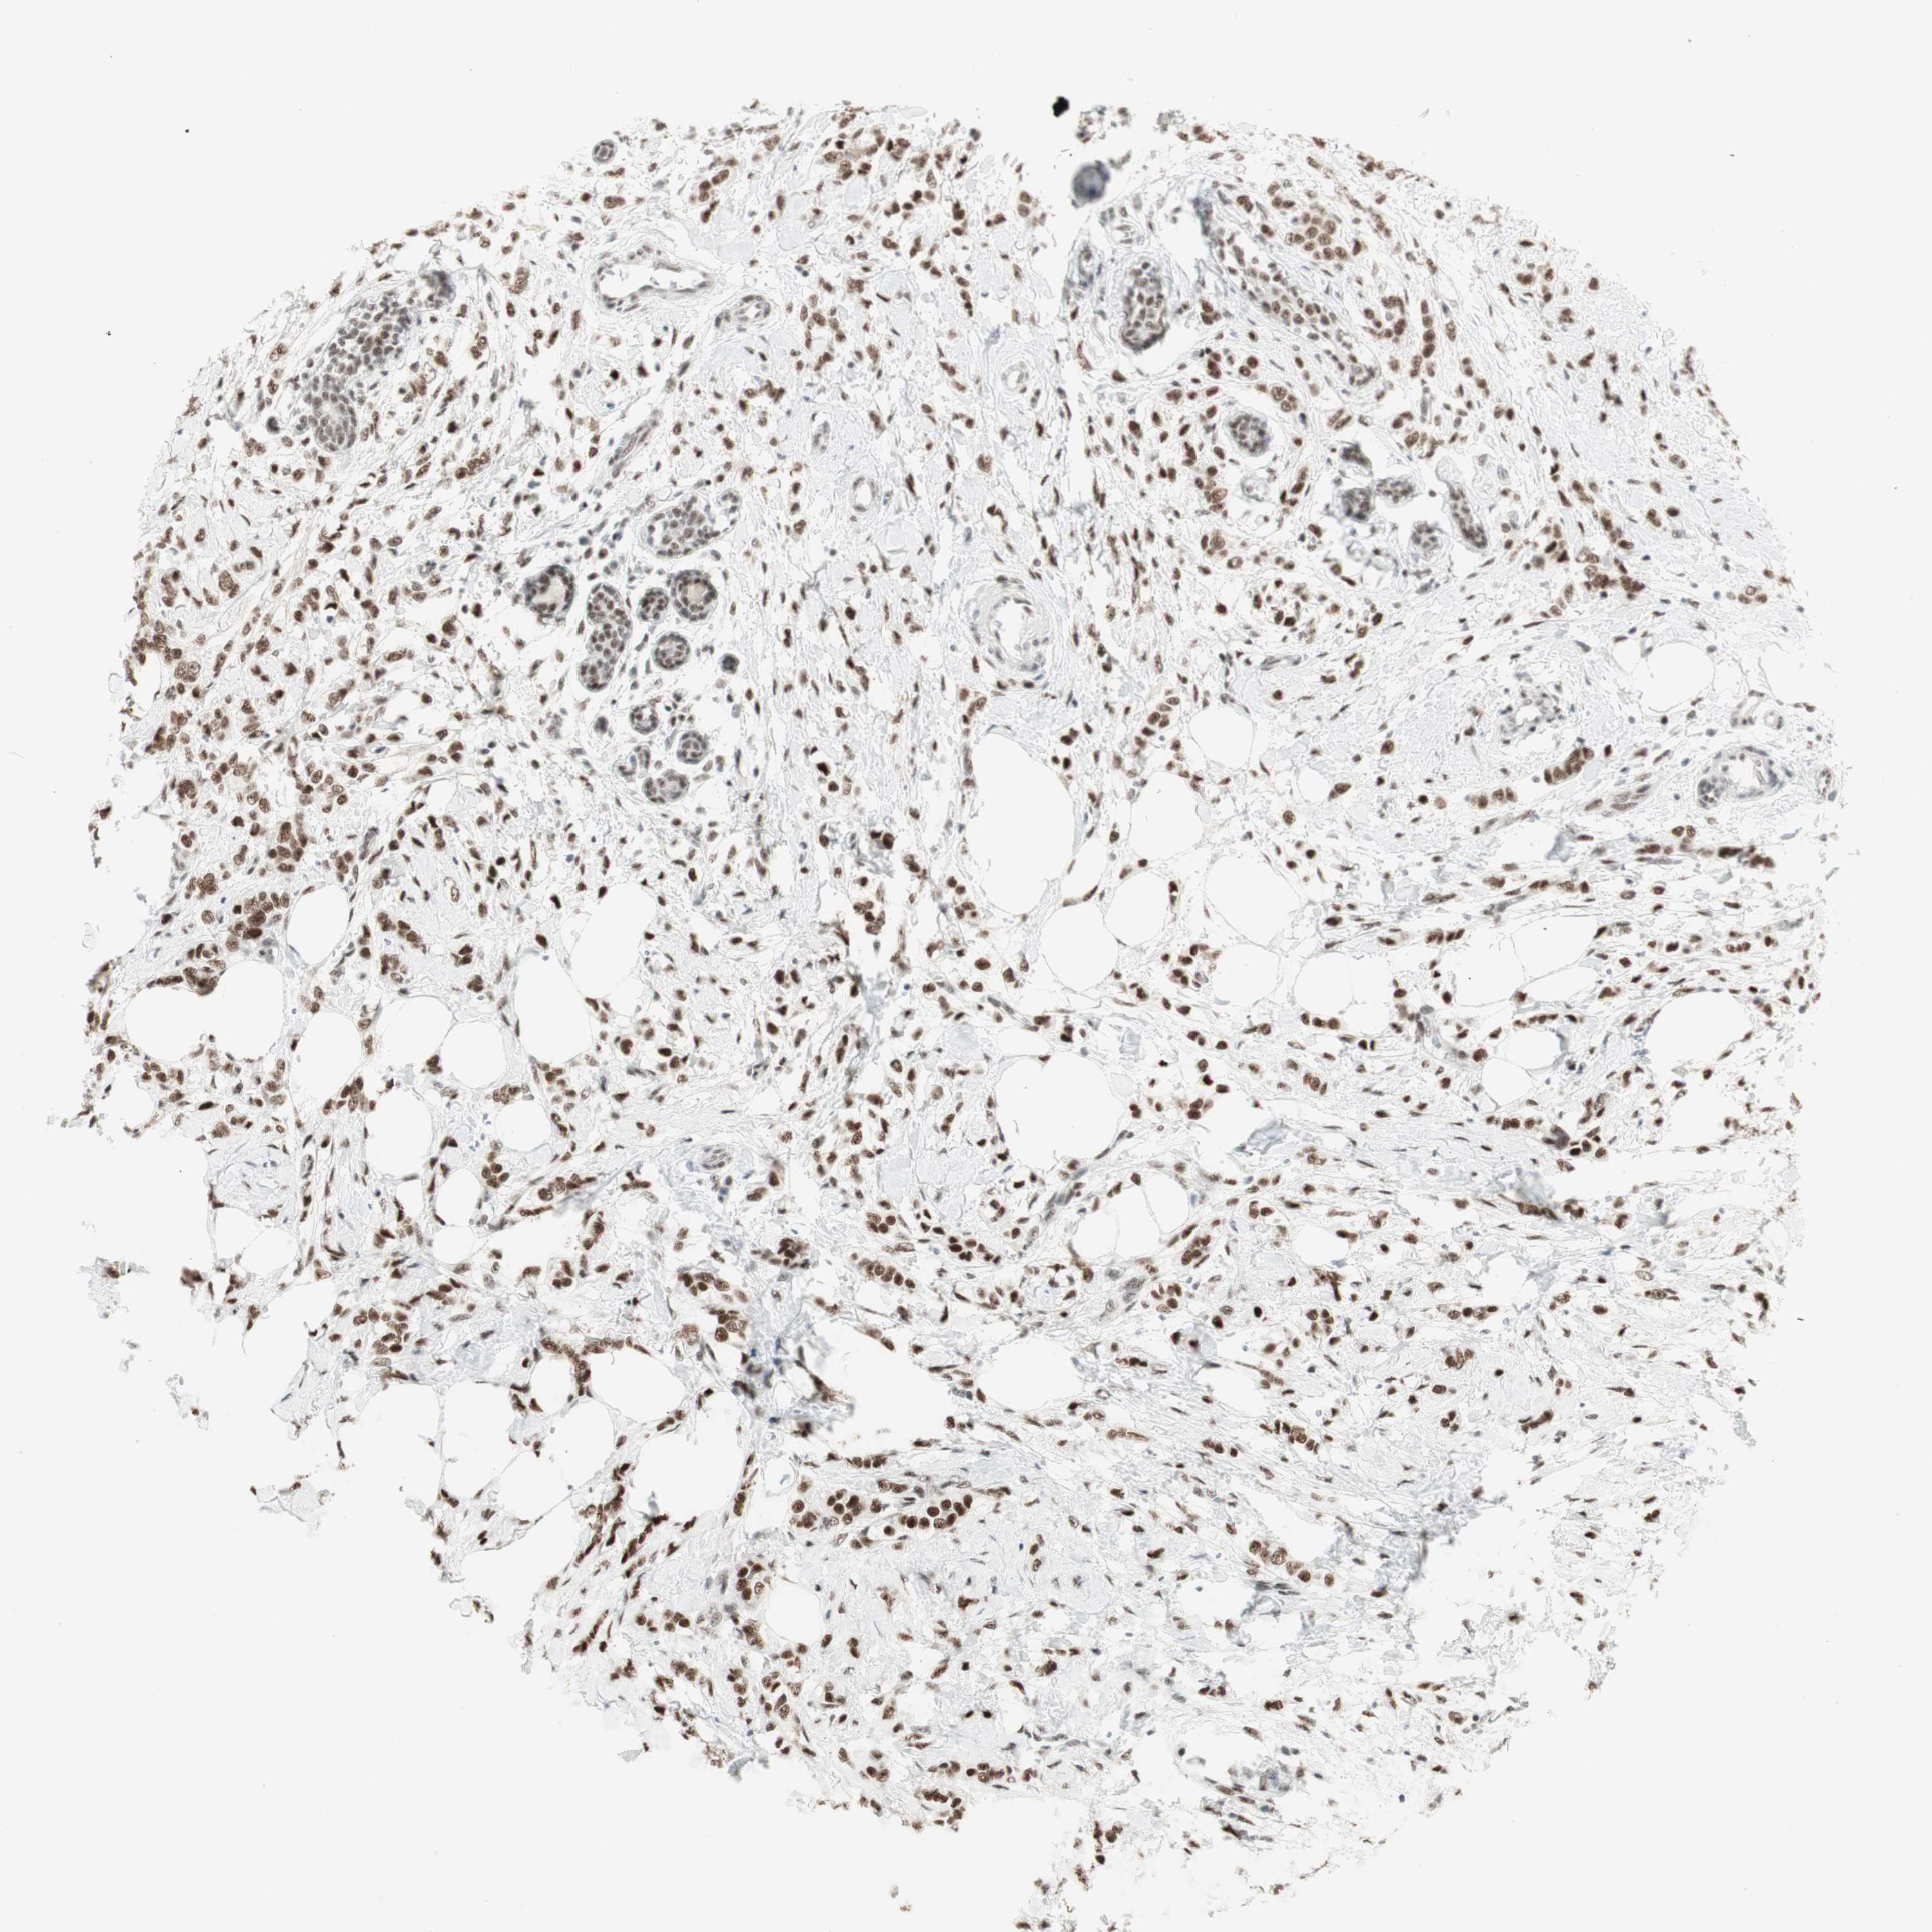

CANCER BREAST CANCER Show tissue menu

BRCA TCGA BRCA VALIDATION PROTEIN EXPRESSION